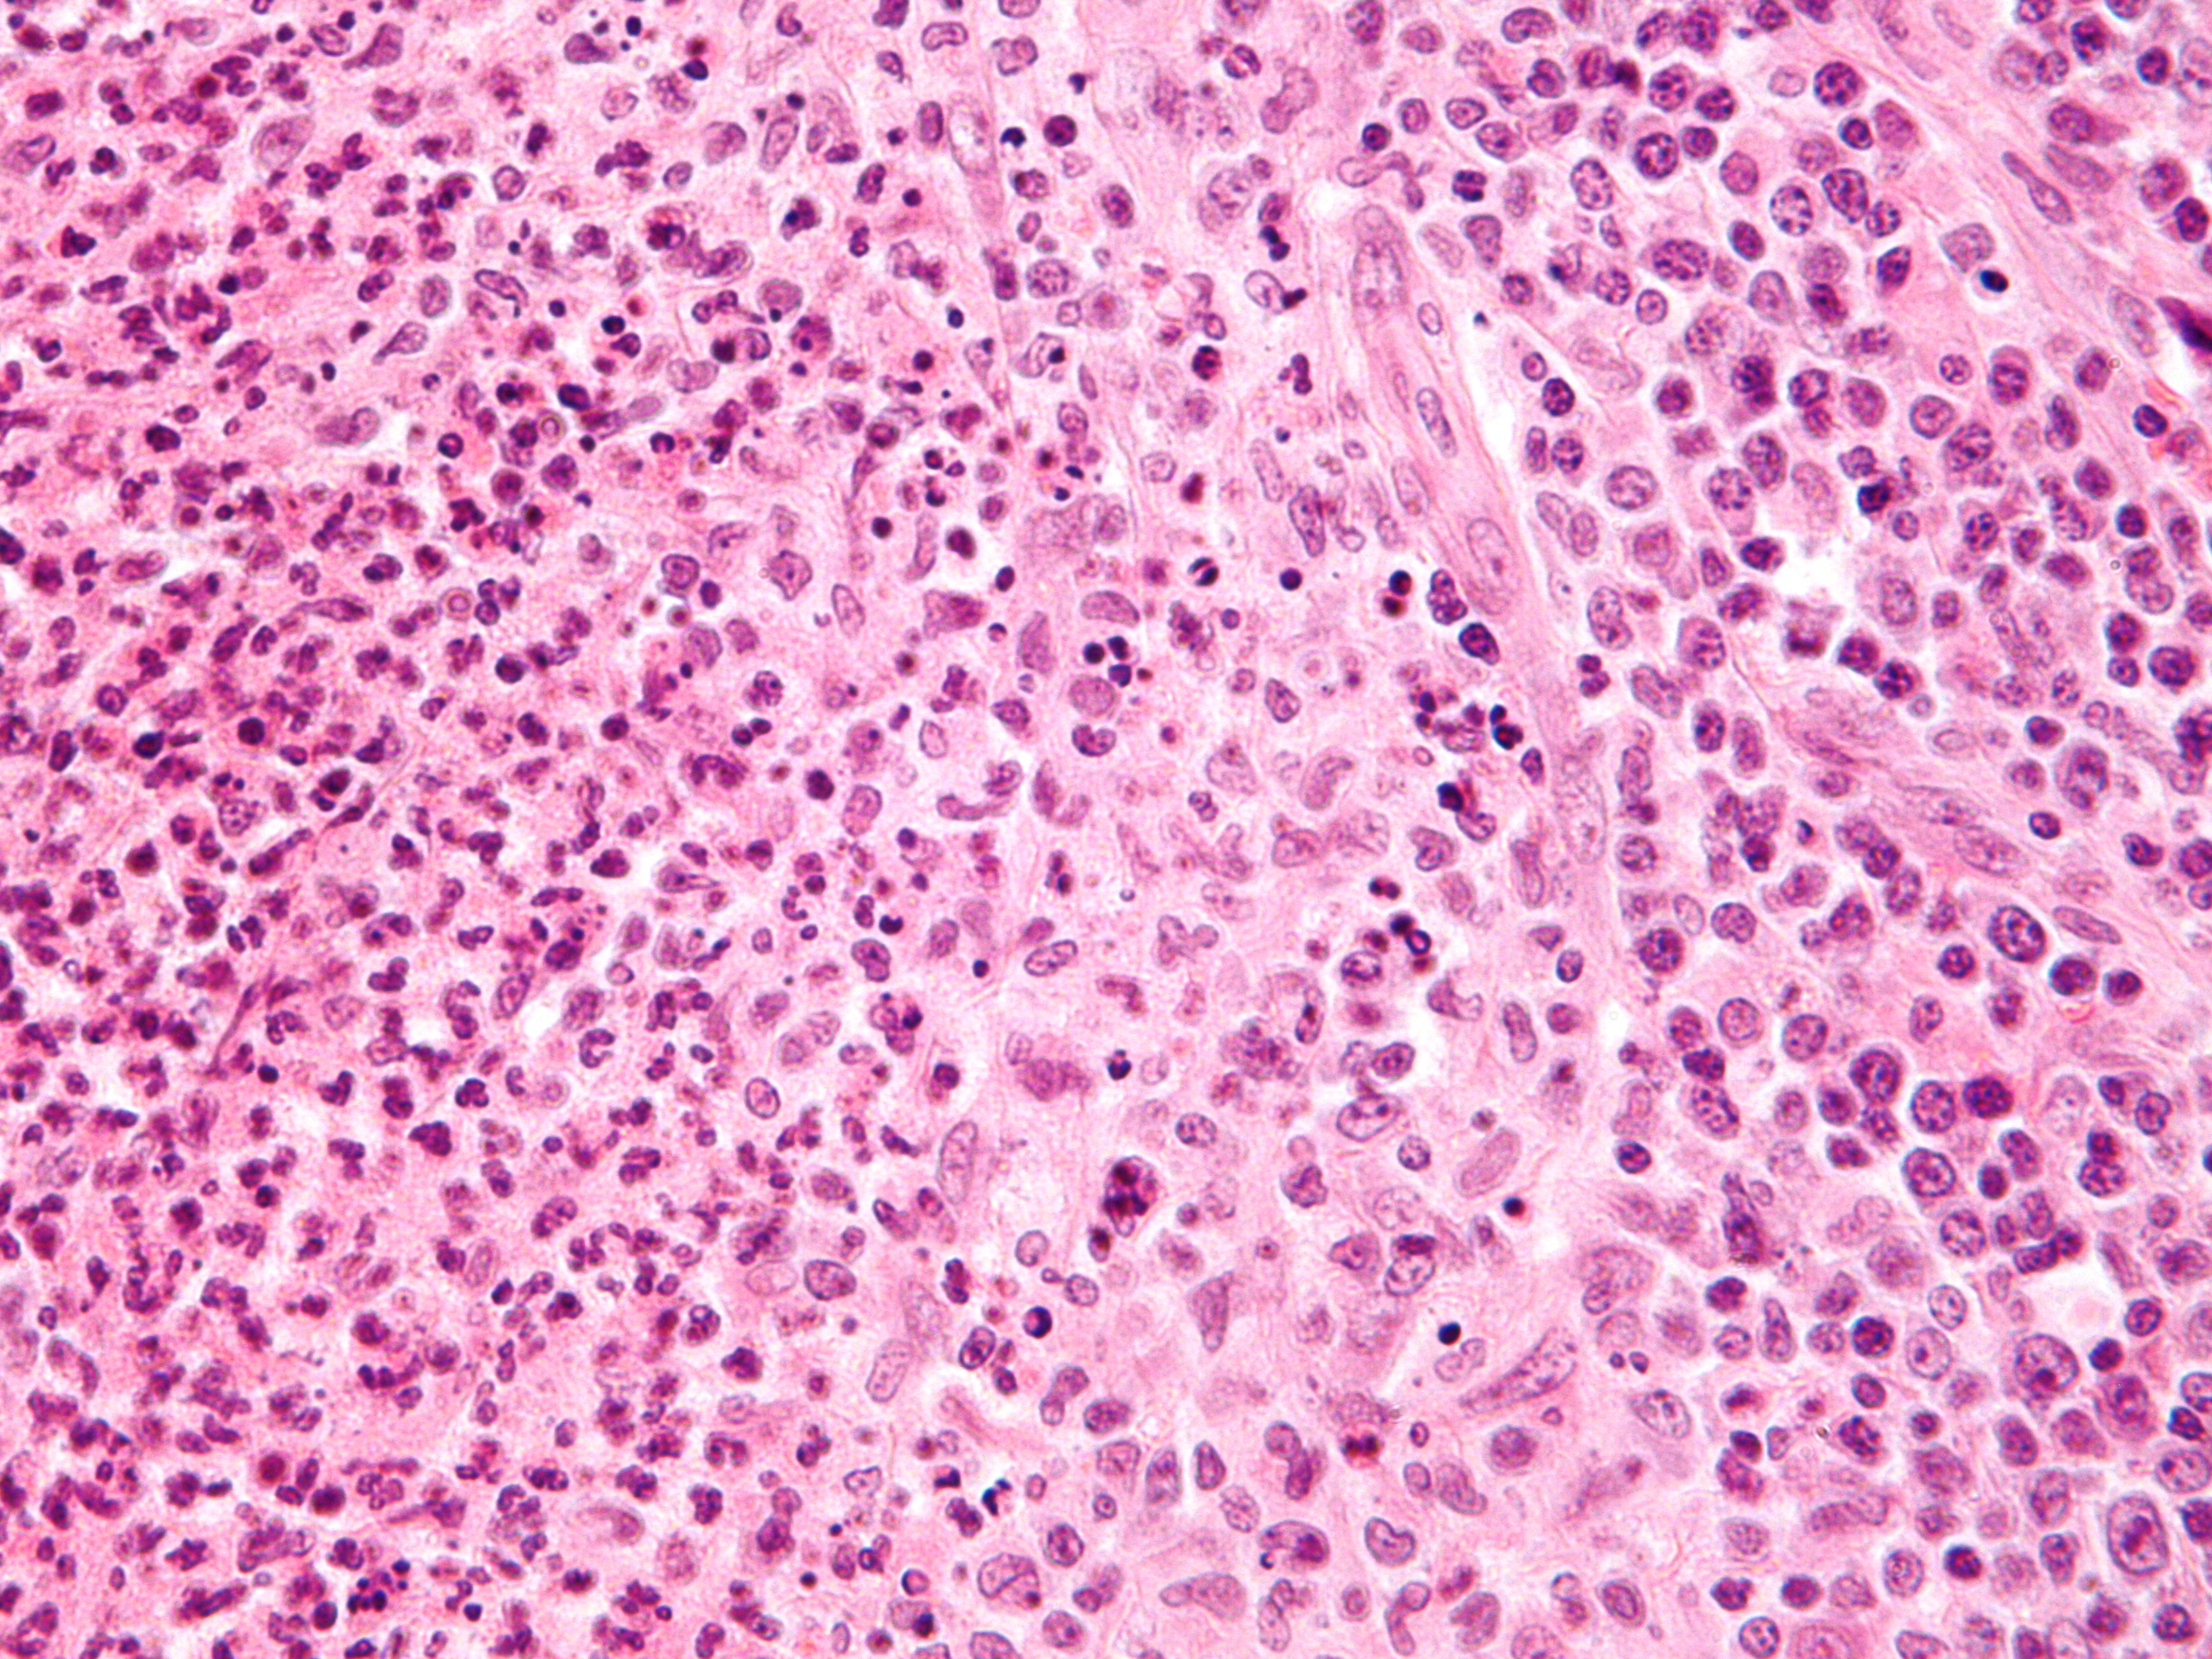

![Cat scratch disease, lymphoreticulosis benigna (click on photo to enlarge) [source: Michael Bonert (Nephron) - Wikimedia - Creative Commons License 3.0] Cat scratch disease, lymphoreticulosis benigna](../../../images/cat-scratch-disease-3z.jpg) |

![Cat scratch disease, lymphoreticulosis benigna (click on photo to enlarge) [source: Michael Bonert (Nephron) - Wikimedia - Creative Commons License 3.0] Cat scratch disease, lymphoreticulosis benigna](../../../images/cat-scratch-disease-4z.jpg) |

| cat-scratch disease |

cat-scratch disease |

PA-Foto's: Michael Bonert (Nephron) - Wikimedia (Creative Commons License

3.0).